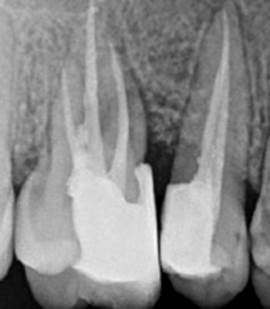

After 4 weeks, surgical intervention was carried out. Under local anesthesia a full thickness mucoperiosteal flap was reflected to entirely expose the underlying bony defect (Figure 3). Scaling and root planing was again carried out with osteoplasty to make sure the site becomes clean and non-infected. Freeze-dried bone allograft (surreoss) 0.5cc powder was condensed into the bone defect (Figure 4) and 1x2cm Acellular Dermal Matrix Membrane (Surederm) was placed over the graft area to prevent the epithelial cell migration (Figure 5). Finally, interrupted silk (4/0) suture were placed to approximate the soft tissue (Figure 6). Post-operative instructions were given and patient was directed to use chlorhexidine gel and rinse three times for a period of 15 days and suitable antibiotics were prescribed for five days. As the prognosis of tooth was highly questionable patient was recalled on follow up after 1 week, 2 weeks and 4 weeks. After 3-months’ patient’s intraoral radiograph showed remarkable improvement in regard to bone repair and patient’s satisfaction (Figure 7). Clinical evaluation on 3-month, 2-year and 5-year recall exhibited marked reduction in pocket depth up to 12mm with radiographic evidence of further hard tissue repair (Figure 8). A 5-year recall showed a stable probing depth of 3 mm with functionally standing in her oral cavity despite the fact that she refused to have a crown on the treated tooth (Figure 9).

In this case, after careful clinical and radiographic examination, the two adjacent teeth # 15 and 16 were found insensible to thermal tests which led to establish diagnosis of pulp necrosis in the affected teeth. The RCT of the affected teeth was imperative to perform before periodontal correction. Following RCT, the patient’s teeth were meticulously scaled and root-planed to further lower the bacterial load from the periodontal lesion site as RCT followed by NSPT exhibits improvement of clinical parameters long with alveolar bone creation (8).